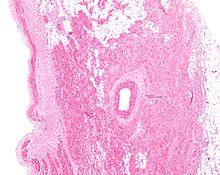

Figure 2: Low magnification stained image of the SA node (center-right on image) and its surrounding tissue. The SA node surrounds the sinoatrial nodal artery, seen as the open lumen. Cardiac muscle cells of the right atrium can be seen to the left of the node, and fat tissue to the right.

The cells of the SA node are spread out within a mesh of connective tissue, containing nerves, blood vessels, collagen and fat. Immediately surrounding the SA node cells are paranodal cells.[2] These cells have structures intermediate between that of the SA node cells and the rest of the atrium.[6] The connective tissue, along with the paranodal cells, insulate the SA node from the rest of the atrium, preventing the electrical activity of the atrial cells from affecting the SA node cells.[2] The SA node cells are smaller and paler than the surrounding atrial cells, with the average cell being around 8 micrometers in diameter and 20-30 micrometers in length (1 micrometer= 0.000001 meter).[7] Unlike the atrial cells, SA node cells contain fewer mitochondria (the power plant of the cell), fewer myofibers (the contractile machinery of the cell), and a smaller sarcoplasmic reticulum (a calcium storage organelle that releases calcium for contraction). This means that the SA node cells are less equipped to contract compared to the atrial and ventricular cells.[8]